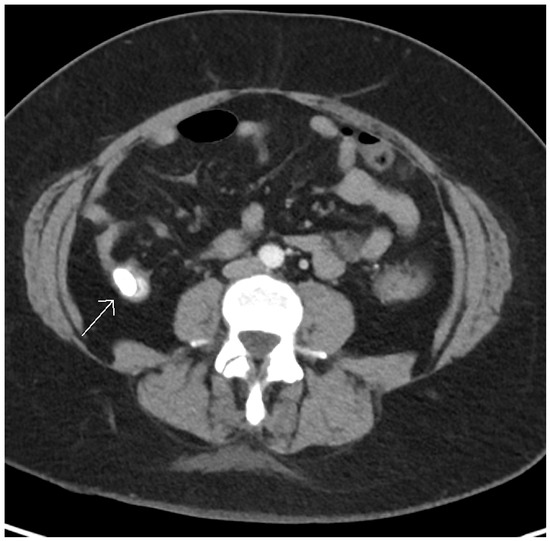

Case Summary